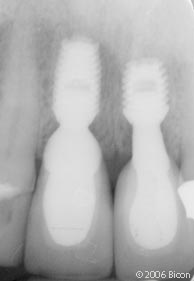

53. |

用两个6.0mm x 5.7mm短种植体支撑两颗一体化基台冠修复左下颌第一和第二磨牙。 |